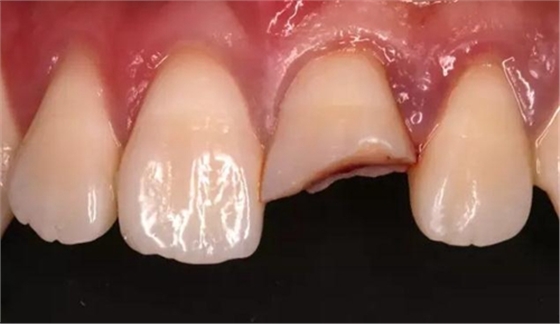

斷冠

折斷之牙體嚴(yán)重脫水,呈白堊色,斷端對(duì)位后吻合度較好,僅少許牙體缺損。